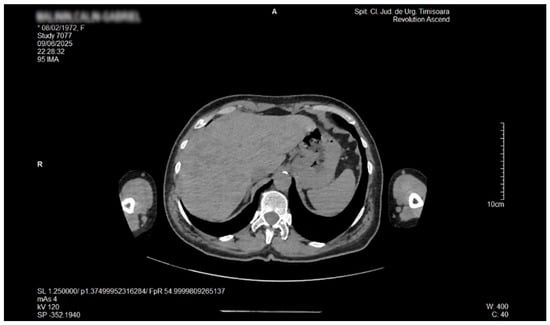

Liver Lipodystrophy in Barraquer–Simons Syndrome: How Much Should We Worry About?

Lipodystrophy is a rare group of metabolic disorders characterized by the abnormal distribution of body fat, which can lead to various metabolic complications due to the body’s inability to adequately process carbohydrates and fat. We report the case of a female, aged 53 years, who was admitted as an outpatient for progressive weight loss of the upper part of the body (face, neck, arms, and chest), dyspeptic complaints, fatigue, mild insomnia, and anxious behavior. Her medical history was characterized by the presence of dyslipidemia, hypertension, and a minor stroke episode. However, she denied any family-relevant medical history. Although the clinical perspective suggested a possible late onset of partial acquired lipodystrophy, due to the imaging exam that revealed an enlarged liver with inhomogeneous structure with multiple nodular lesions, scattered over both lobes, a lot of lab work-ups and complementary studies were performed. Eventually, a liver biopsy was performed by a laparoscopic approach during cholecystectomy, the histology consistent with metabolic disease-associated steatohepatitis (MASH). In conclusion, given their heterogeneity and rarity, lipodystrophies may be either overlooked or misdiagnosed for other entities. Barraquer–Simons syndrome (BSS) may be associated with liver disease, including cirrhosis and liver failure. Liver lipodystrophy in BSS may sometimes feature steatosis with a focal, multi-nodular aspect, multiplying the diagnostic burden. Liver lipodystrophy may manifest as asymptomatic fat accumulation but may progress to severe conditions, representing one of the major causes of mortality in BSS, apart from the cardio-vascular comorbidities. Given the potential of severe outcomes, it is mandatory to correctly assess the stage of liver disease since the first diagnosis. Full article

Figure 1